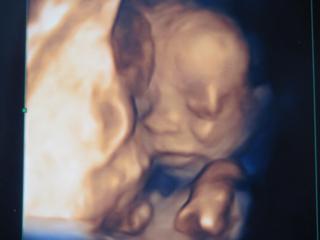

@janka273 nie ja sama chcem ist na 3D este som to nevidela na ziadnom mojom dietatku a budem mat aj dvd tak sa tesim skoda ze az 5.1.